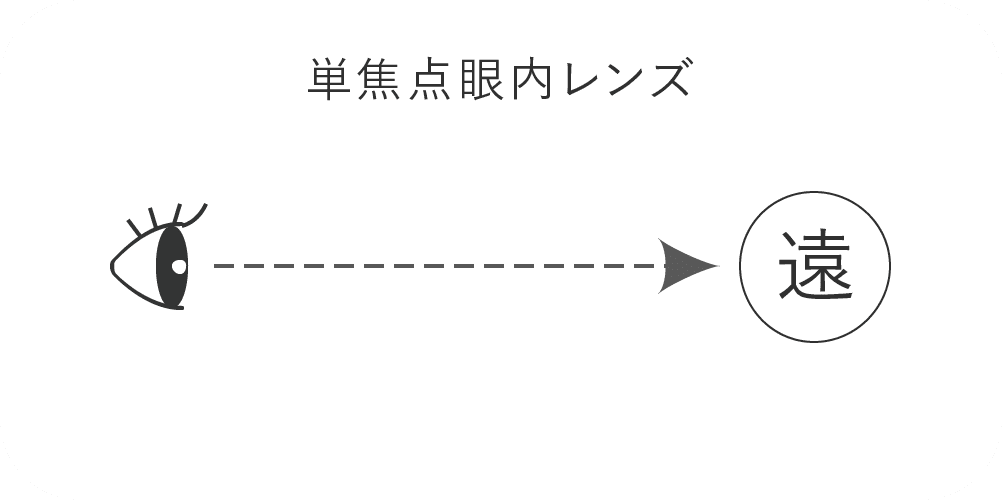

単焦点眼内レンズは、近方・遠方どちらか1点の距離に焦点を合わせた眼内レンズです。

焦点を合わせていない場所は、メガネが必要になります。

- ◯メリット

- 健康保険適用なので費用が抑えられる。

- ピントを合わせた距離はクリア。

- ●デメリット

- 必ずメガネが必要になる。